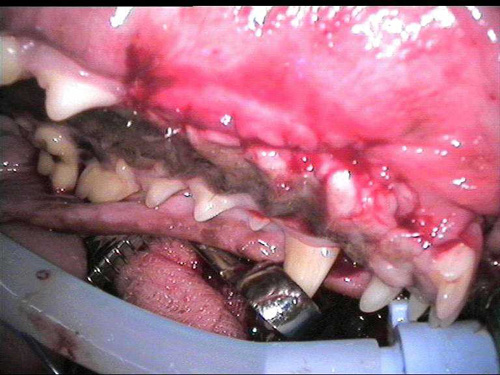

NORMAL MANDIBLE X-RAY DOG

Bess Sanxter

destructive disorder